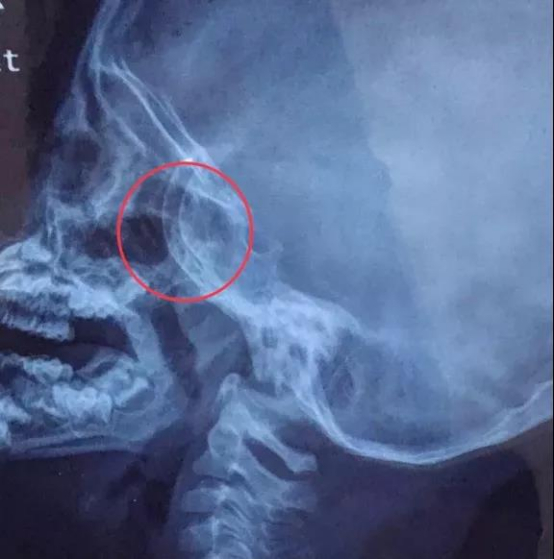

鼻咽侧位片和鼻咽CT可以显示鼻咽顶后壁的病变情况,在耳鼻喉科中应用非常广泛,主要用于诊断儿童的腺体肥大,以及成年人的鼻咽部占位等疾病情况。

*鼻咽侧位片示肥大的腺样体。